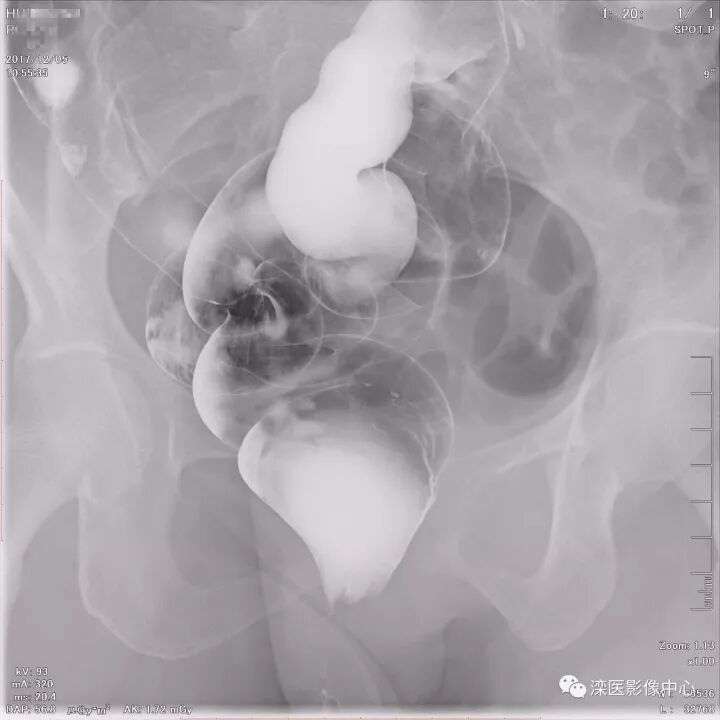

下面请您审阅近期我院影像科开展下消化道双对比造影检查的图像:

(以上图像是对结肠脾曲、横结肠、结肠肝曲的显示)